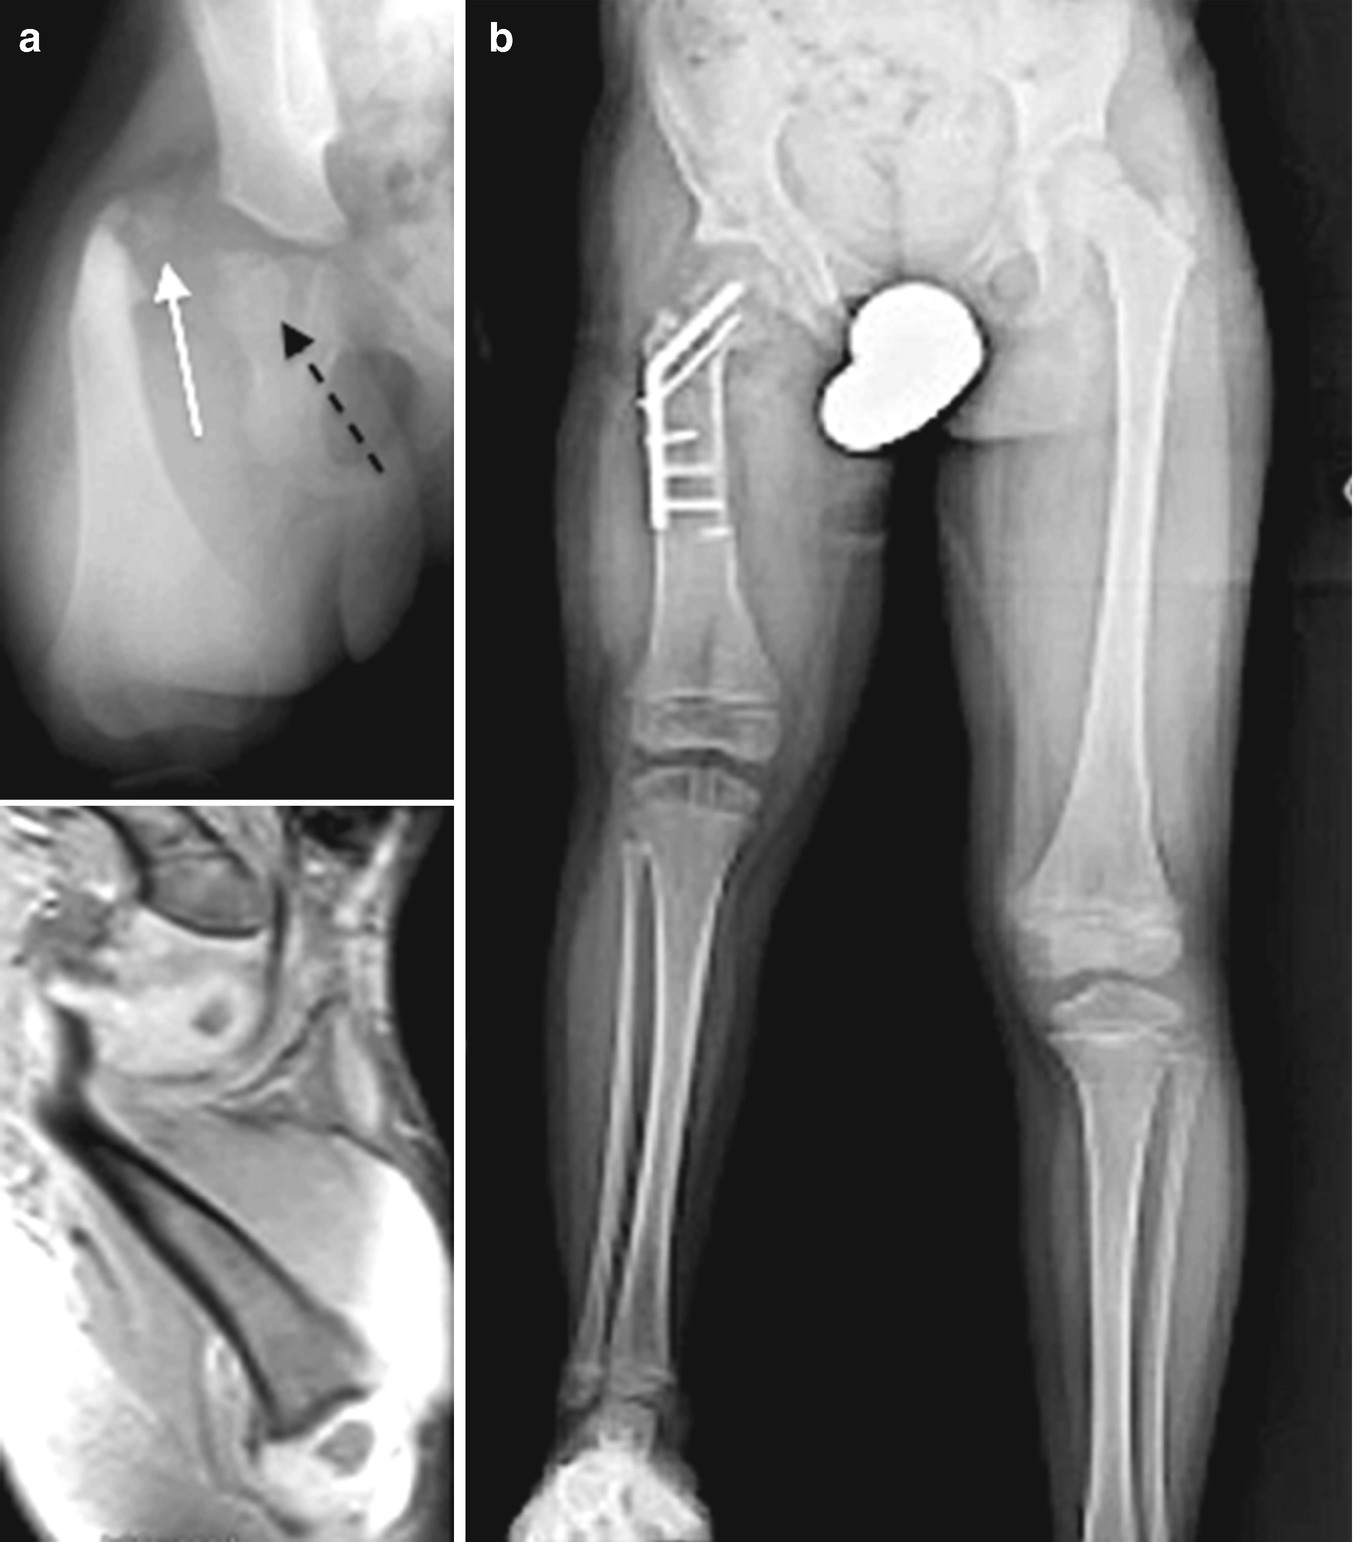

Orthopaedic Surgeon Corrects Rare Leg Deformity Called Miserable Malalignment Syndrome. This study investigates the results of surgical correction of miserable malalignment syndrome associated with significant patellofemoral pain. Surgery is reserved for children older than 8 years of age with external tibial torsion greater than three standard deviations above the mean 40 degrees external.

Bilateral Double Osteotomy In Severe Torsional Malalignment Syndrome 16 Years Follow Up Journal Of Orthopaedics And Traumatology Full Text